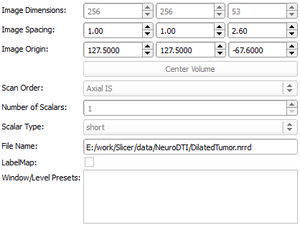

| qMRMLVolumeInfoWidget |

|

A widget that shows volume internal data properties |